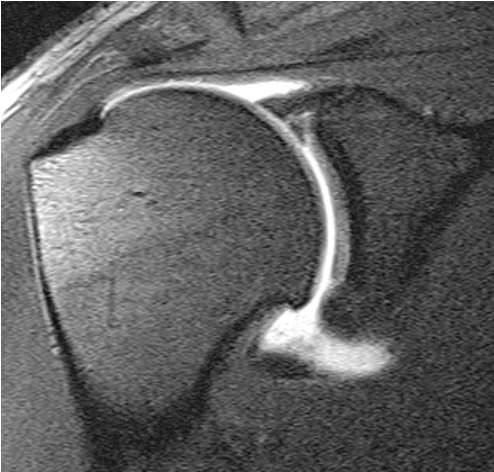

MRI

Exclude rotator cuff tear

Look for cyst / mass / AV malformation at suprascapular notch